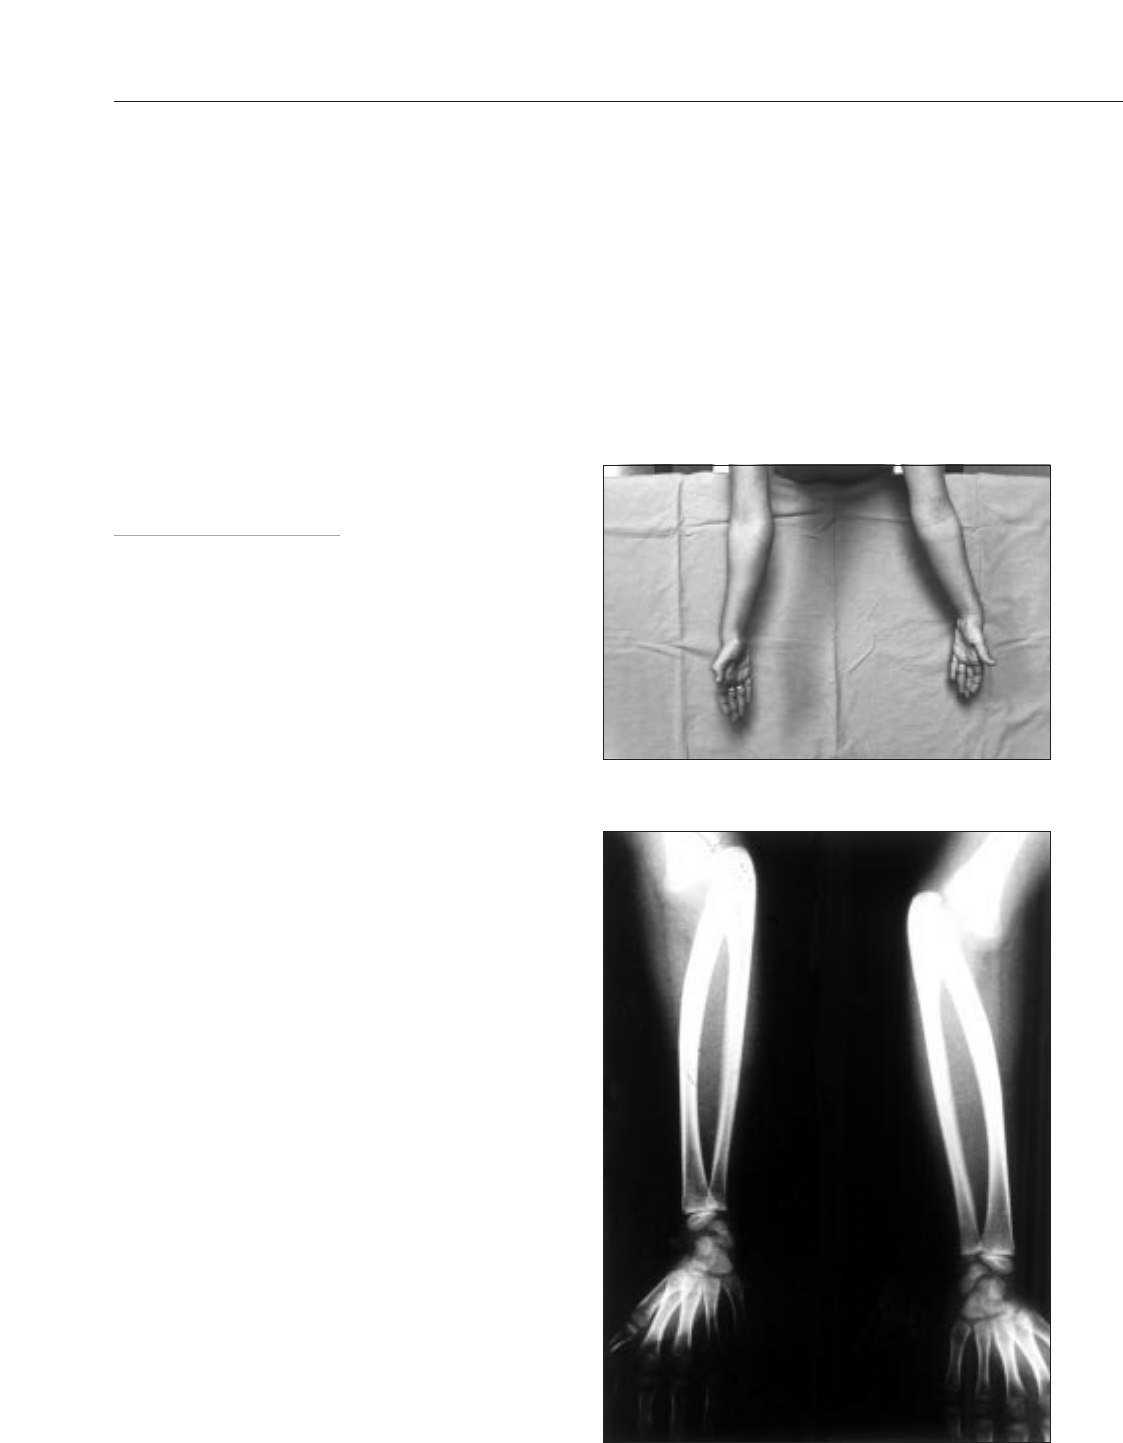

Se presenta el caso de una niña de 6 años. En la revisión de sa-

lud se detecta una dificultad para la pronación y supinación de las

extremidades superiores. Los padres refieren que ya hace algún

tiempo la niña realiza “movimientos extraños” con los hombros en

algunas actividades como llevarse la taza a la boca, coger palomitas

con las dos manos, abrir una puerta y otras acciones habituales.

Antecedentes personales y familiares sin interés. En la exploración

física destacaba una limitación de los movimientos de pronación y

supinación en ambos antebrazos, con un recorrido máximo de 100°,

medidos a la altura de la muñeca (fig. 1). Las radiografías muestran

la presencia de la sinostosis radiocubital bilateral, junto con luxación

posteroexterna de los antebrazos (fig. 2). El resto de articulaciones

están libres. El resto de exploración por aparatos es normal.

Figura 1. Antebrazos en supinación máxima.

Figura 2. Radiografía posteroanterior de los antebrazos.